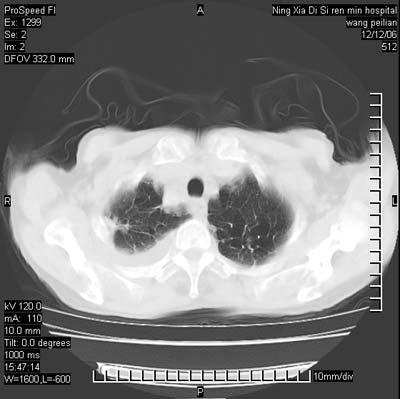

标题: CT5609:胸部:女77 病史不详 [打印本页]

标题: CT5609:胸部:女77 病史不详

两肺可见多个大小不等的结节,左侧有胸水,纵隔淋巴结增大,考虑是细支气管肺泡癌

两肺尖纤维索状影,两下肺结节块状影,且有钙化灶,右胸腔积液。考虑肺结核并胸膜炎。

两肺尖纤维索状影,两下肺结节块状影,且有钙化灶,右胸腔积液。考虑肺结核并胸膜炎肺间质纤维化

考虑:1、慢性支气管炎合并全小叶型肺气肿、间质纤维化;

2、双肺结核;

3、右侧胸膜炎(积液)。

1、双肺继发型肺结核(以纤维、增殖灶为主);

2、右侧胸腔积液;

3、其余符合老年肺改变。

双肺见多个结节状及条索状影,双侧胸腔积液,右侧叶间积液,考虑结核性胸膜炎